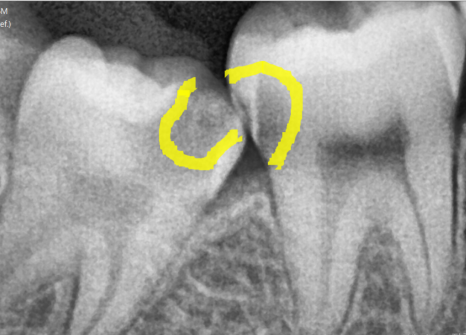

문제는 사랑니 자체보다

바로 앞어금니 상태였습니다.

엑스레이와 입안 사진을 통해 확인해 보니,

앞에 치아까지 충치가 생겨있었습니다.

심지어 충치가 꽤나 많이 진행되어

이미 신경 가까이까지 진행된 상황이었습니다.